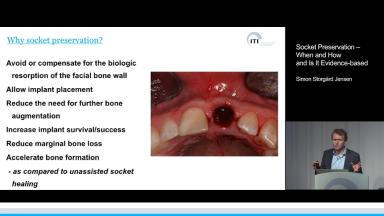

The presentation walks the audience through the healing steps of the post-extraction socket and emphasizes the dimensional ridge alterations. This basic introduction sets the stage for the lecture core, which focuses on the significance of socket management as a staged procedure prior to implant placement. The rationale for treatment and the different techniques and materials are presented along with evidence originating from preclinical and clinical studies as well as recent systematic reviews. This lecture concludes with treatment recommendations for a variety of clinical situations.

- describe socket healing processes

- explain the rationale for socket augmentation

- discuss technique selection for socket augmentation